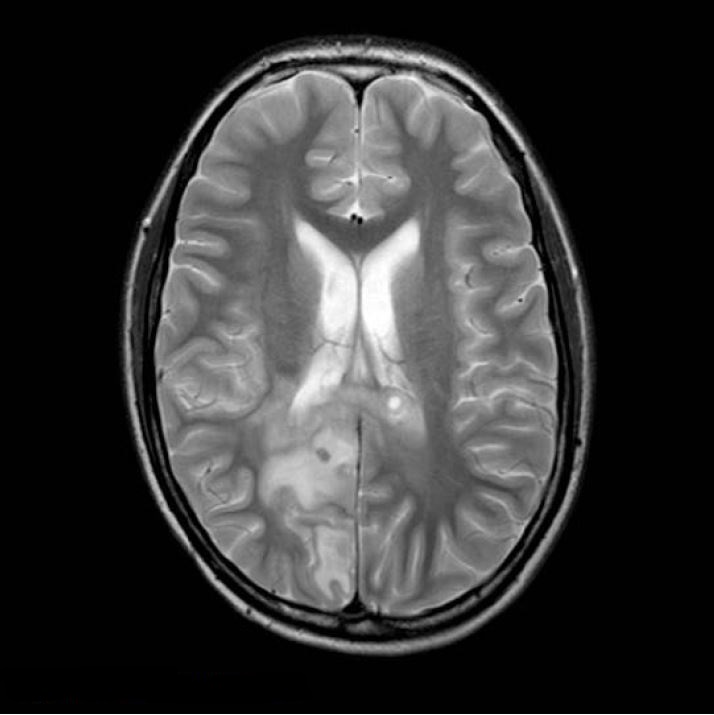

При неврологічному огляді виявлено двобічний набряк зорового нерву, двобічний парез 6-го черепного нерва, геміанопсію. Його одразу направили на МРТ. Було виявлено велике пухлинне утворення, частково геморагічне, у правій тім’яній ділянці з значним мас-ефектом (рис. 1 і 2).

Рисунок 1 T2WI, перше сканування